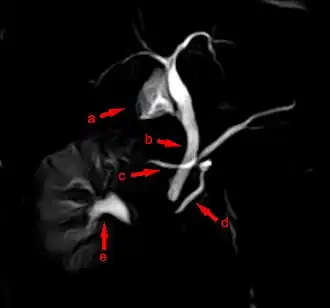

Pancréas divisum en cholangio-IRM

Dans le pancréas divisum complet, le canal pancréatique accessoire de Santorini draine la quasi-totalité du pancréas (corps et queue) alors que le canal pancréatique principal draine la tête de l'uncus[1]. Dans les formes incomplètes, il existe une communication entre ces deux systèmes canalaires (fusion incomplète).